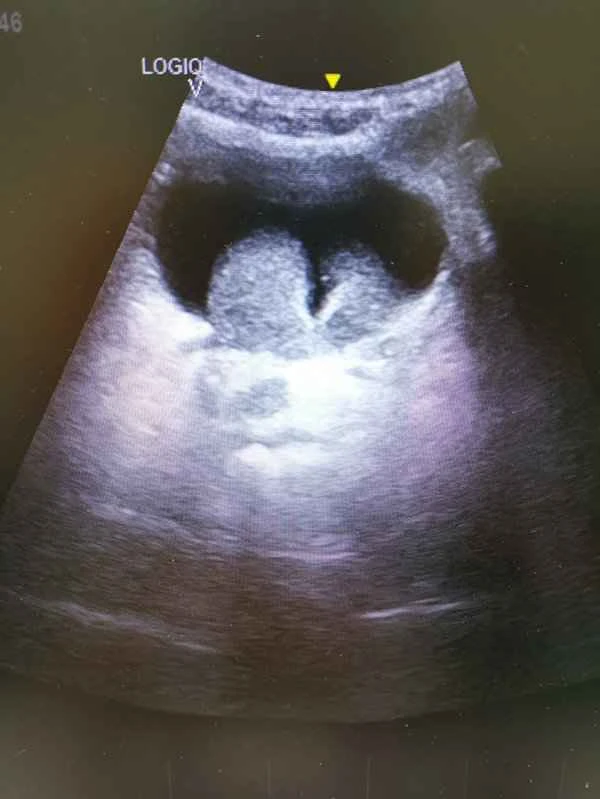

A scrotal ultrasound is a non-invasive examination used to observe the structures within the scrotum, including the testes, epididymis, and spermatic cord. It can help doctors diagnose various diseases, such as testicular torsion, epididymitis, and testicular tumors. The importance of this examination lies in its ability to help detect and diagnose diseases of the male reproductive system at an early stage, thus allowing patients to receive the best possible treatment.

A scrotal ultrasound examination typically involves scanning the scrotum with an ultrasound machine. The doctor then uses the images to determine if any abnormalities are present. This examination works by utilizing the physical properties of ultrasound waves; it generates images based on the differences in how different tissues reflect ultrasound waves, allowing doctors to observe subtle structural changes within the scrotum. While the procedure is relatively simple, the results are crucial for diagnosis and treatment.